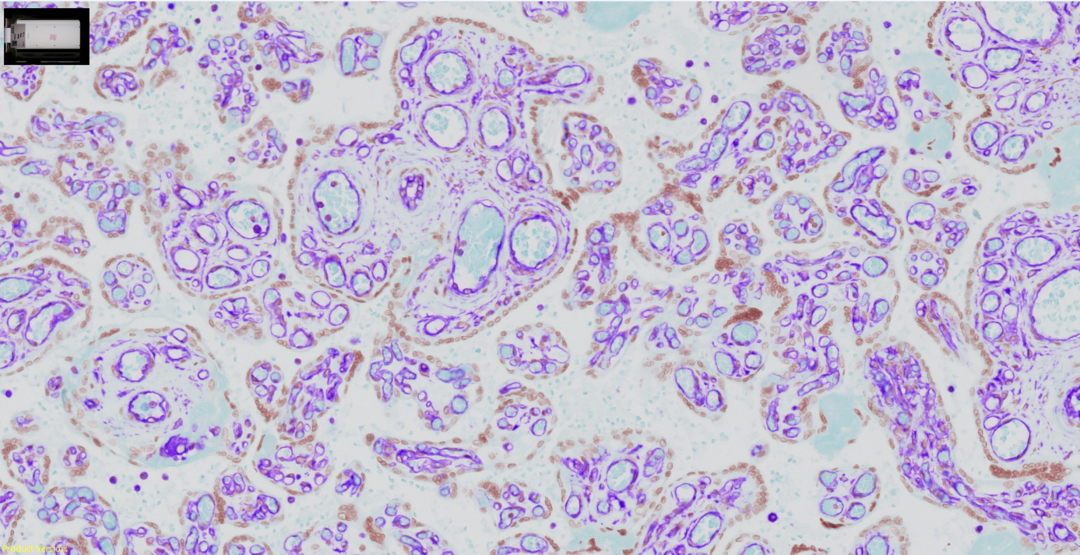

清晰捕捉各种组织和染色的细节

胎盘波形蛋白(Vimentin)的免疫组化染色(IHC)